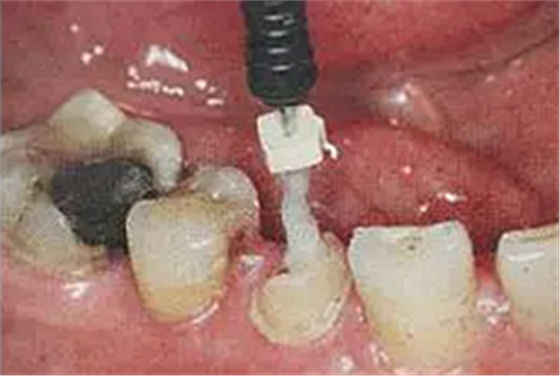

6. 纖維樁的試放和裁戴

纖維樁試放時(shí)應(yīng)用鑷子夾持將其插入預(yù)備的根管樁道中(這涉及無菌觀念和操作),就位時(shí)無阻力可稍有錮住感。

(鑷子夾持(正確))

(污染手套夾持(錯(cuò)誤))

(技工鉗裁剪(錯(cuò)誤))

試放后應(yīng)按所需長度用細(xì)粒金剛砂車針切割裁剪。

(粘樁堆核固化后裁剪)

為防止裁剪過程中有可能造成樁表面的污染,可以粘結(jié)固位后再進(jìn)行裁剪。

操作時(shí)。光固化燈應(yīng)在樹脂核成形后,頰、舌、合面分別光照20秒,在完成預(yù)備體后將其磨除。